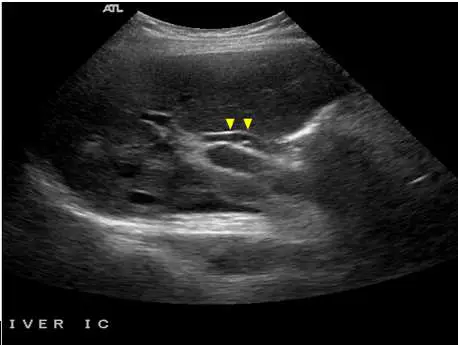

下圖中箭頭所指的是下列何者?

影像分析:

圖片為腹部超音波影像(ATL 廠牌機器,標示 LIVER IC 肝臟肋間切面)。影像中央偏上方可見兩個黃色箭頭(arrowheads),指向一個橢圓形至管狀的無回音(anechoic)結構,其管壁呈現明顯的高回音(hyperechoic)雙層管壁外觀,內腔清晰呈液體特性。

此結構位於肝門部,鄰近一個較大的圓形無回音管狀結構(即門靜脈)。根據位置關係:

- 門靜脈(portal vein):最大的管狀無回音結構,位於後方中央(Mickey Mouse 臉部)

- 肝動脈(hepatic artery):門靜脈前方偏內側(左耳),較小,搏動性(需 Doppler 確認)

- 總膽管(common bile duct):門靜脈前方偏外側(右耳),較小,無血流,管壁較厚且呈高回音

箭頭所指之結構具有以下特徵:雙層高回音管壁、無回音內腔、無搏動性血流訊號,符合總膽管的